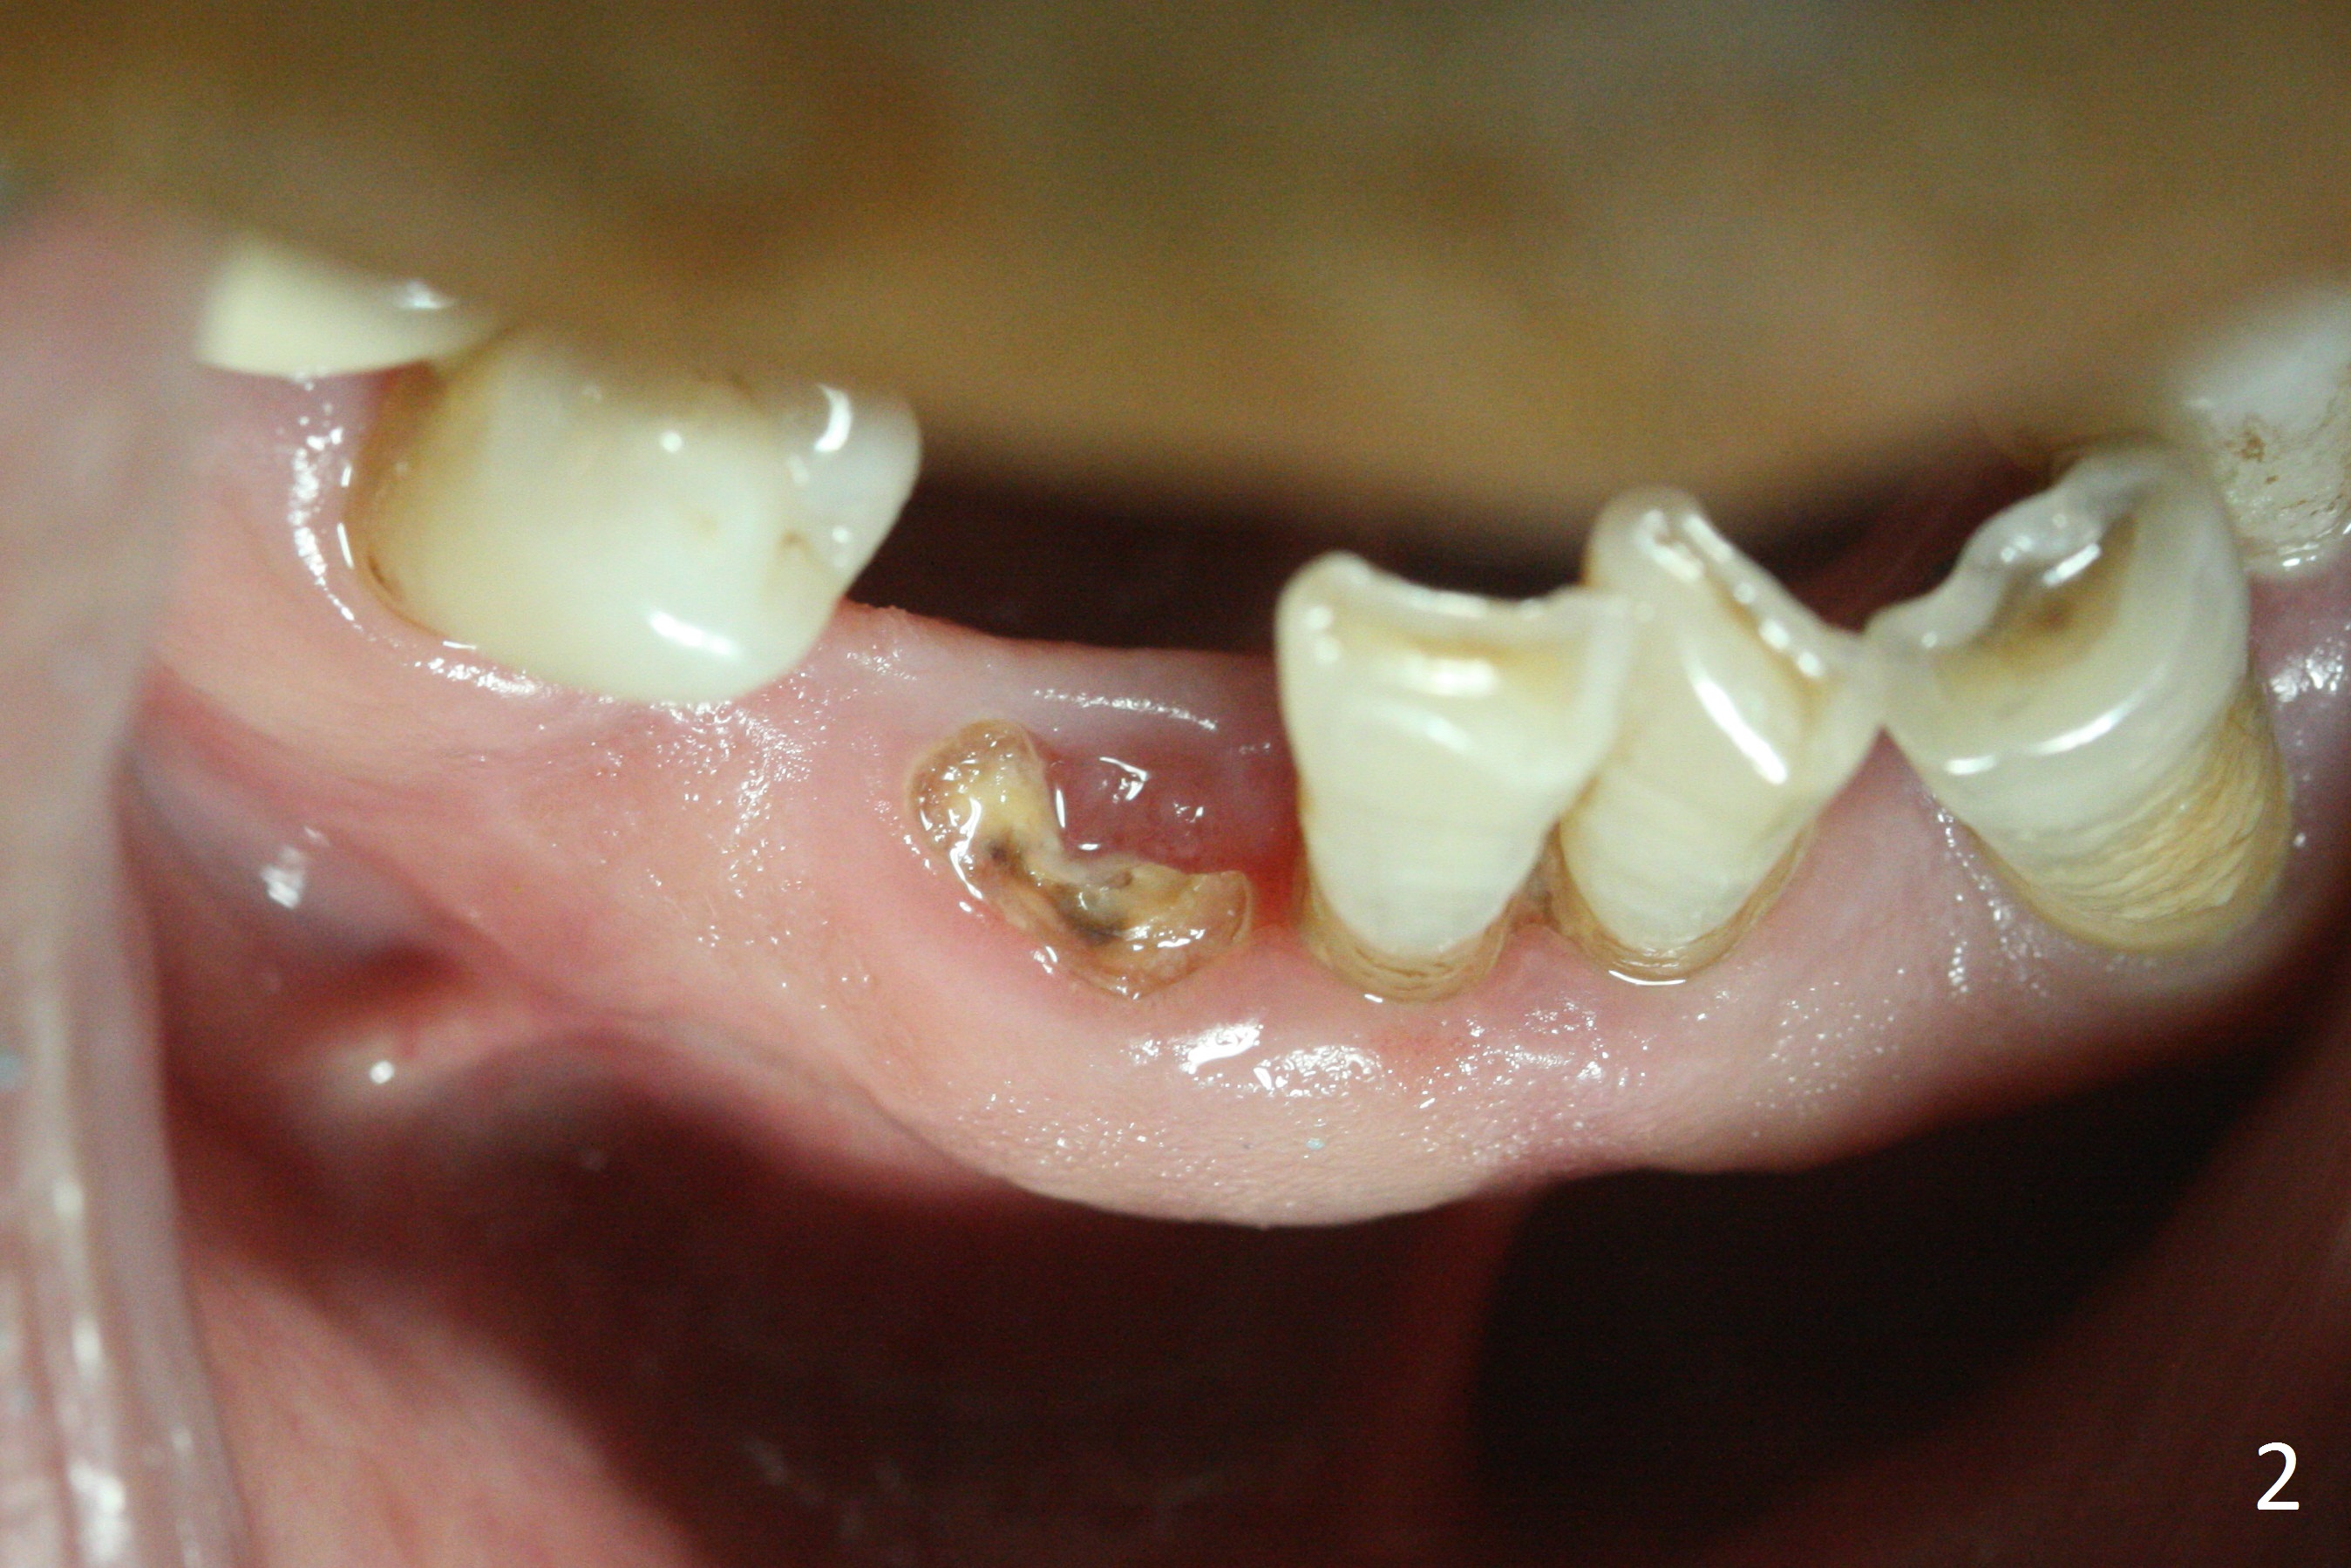

The lower dentition is special, consisting of a residual root (Fig.1 ^), 2 incisor (I), 1 canine (C), 1 premolar (P) and 1 molar (M). The residual root looks like an incisor with rotation of 90º (Fig.2,3). Osteotomy is initiated (Fig.4) for a 3x16(2) mm 1-piece implant (Fig.5 with 45 Ncm). The implant is being placed as distal as possible (Fig.4 arrow) so that a large canine-like provisional is to be fabricated in the large edentulous space (Fig.8,9) after bone graft (Fig.6,7 *). The gingiva around the provisional (Fig.10 P) remains healthy 11 days postop with occlusal clearance against the opposing dentition (Fig.11). The implant threads are not exposed with the help of bone graft 3 months 1 week postop (Fig.12). The gingiva around the implant is healthy (Fig.13). Soft tissue socket is formed by the provisional (Fig.14 *).